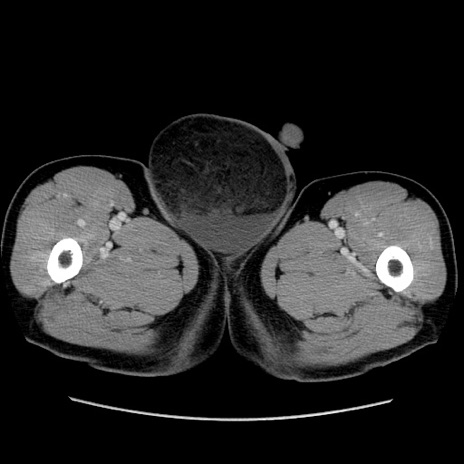

症例34(横断像)

【症例】60歳代 男性

【主訴】右鼠径部膨隆

【現病歴】1年程前より右鼠径部膨隆あり。自己にて還納可能だったため放置していた。3時間前より右鼠径部の脱出を認め、還納困難となり受診。

【既往歴】高血圧

【身体所見】右鼠径部に小児頭大の膨隆あり。弾性硬であり、用手還納は困難。左鼠径部にも膨隆を認める。脱出はなし。

【データ】WBC 15500、CRP 測定なし